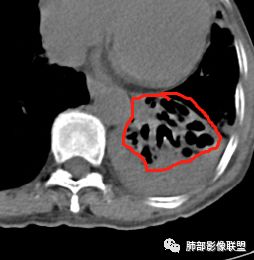

支气管扩张、扭曲成团,附近钙化灶

肿瘤会这样吗?

这例左下叶的体积是整体缩小的,左下叶的支气管主干稍微小一点点,然后左上叶的下舌段也有类似的病灶,然后我们看到一团乱的支气管扩张,但它有特点,边缘凹凸不平。那什么样的支气管扩张边缘会如此凹凸不平呢,等我截个图:

看最后一幅图,上面这个支气管,有可能是淋巴瘤,为什么?他的支气管稍扩张,直达远端、实变。

首先这幅图支气管很多地方是扭曲的,远端扩张的特别厉害。如果是肿瘤,首先考虑淋巴瘤,因为支气管可直达远端,稍扩张,但是它的前提是周围要实性占位的,而且它不会这样扭曲变形。我们看这个病例的支气管扩张,它支气管扩张占大部分区域,中间稍有些实性的结构,这就不符合了。这幅图你会发现所有支气管都是扩张的,实性部分偏少,外围胸水。所以我更倾向慢性炎性病变,能够引起支气管扩张的炎性病变有哪些?结核?NTM?支扩伴感染?大方向是慢性炎性病变。这些左下肺播散出来的病灶,咳中等量黄浓痰,我考虑还可能合并细菌感染。

1.双肺斑片影、大小不等结节影,边界不清,密度较均一,钙化不多见,可见树丫。

2.左肺下叶大范围病灶,其间柱状支气管扩张相当显眼。

这些都支持慢性炎性改变。

5.影像学改变可以用非结核分枝杆菌感染解释。